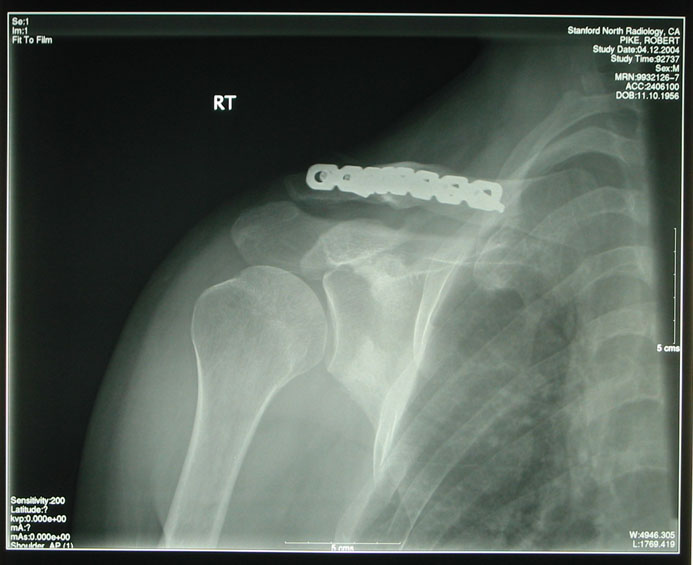

通过仔细翻阅他在贝尔实验室的个人主页,发现 2003 年发起了一次严重车祸 —— 下坡的时候他从自行车上摔了下来!摔断了三根肋骨、锁骨碎裂、肩胛骨纵向分裂。辛亏当时带了头盔,不然有没有今天的 Go 语言都不好说。事后他饶有兴趣地将自己骨头的 X 射线底片放到了个人博客上和粉丝们一起仔细研究观赏。